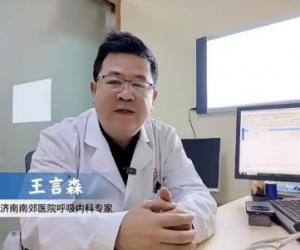

- 11-24省医三院王言森教授长期坐诊济南南郊医院 守护秋冬呼吸道健康

- 11-05秋冬养肺正当时!济南南郊医院王言森教授提醒:肺结节人群需关注这些信号

- 10-27秋冬咳嗽高发季 王言森教授:辨证施治+精准诊断,中西医结合效果佳

- 11-24省医三院王言森教授长期坐